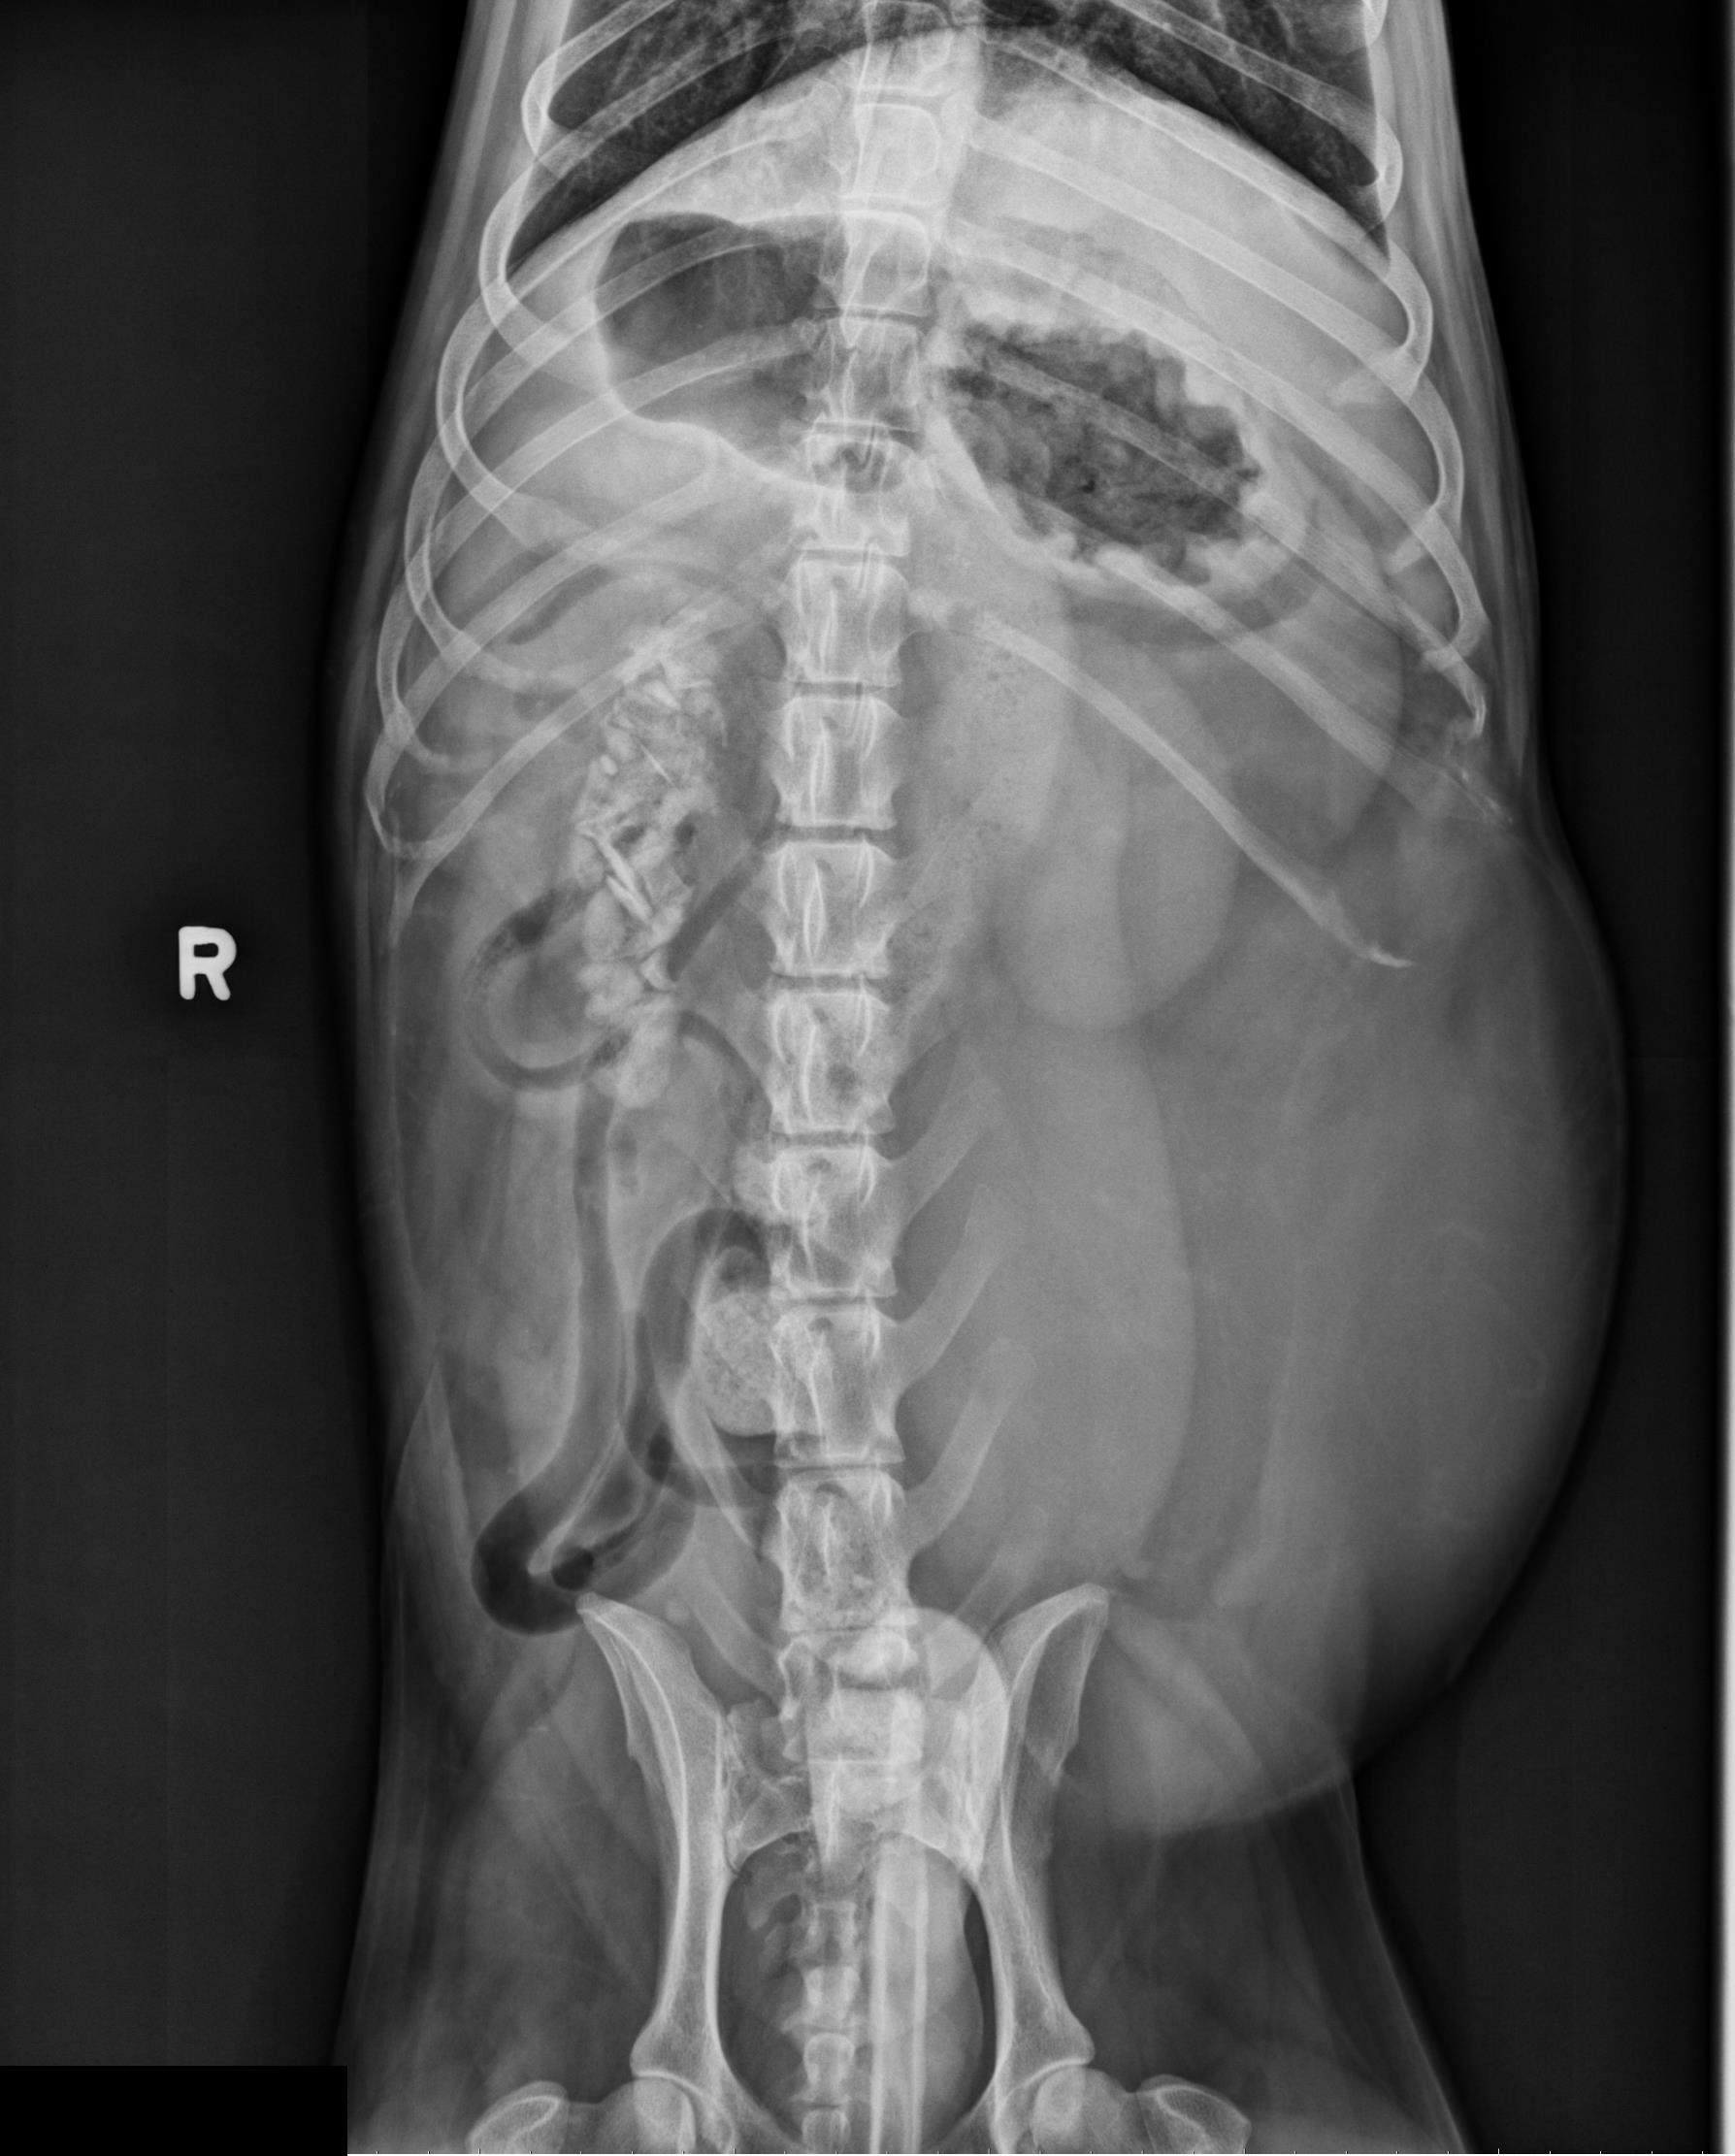

Er is een artefact door natte vacht langs de ventrale buik. De serosale details zijn normaal.

In het linker mid-ventrale abdomen bevindt zich een grote, ovale structuur met vetdensiteit van ongeveer 20 x 15 cm. Deze structuur veroorzaakt een laterale deviatie van de linker buikwand, een naar rechts en dorsaal verplaatste colon en dunne darmen, en een craniale verplaatsing van de staart van de milt.

De maag is matig met gas gevuld. De dunne darmen bevatten diffuus gas en vloeistof/weke delen densiteit en hebben een normale en uniforme diameter. In het colon zijn fusiforme tot rechthoekige botdense structuren zichtbaar.

Lever, milt, nieren en urineblaas zijn normaal.

- De grote intra-abdominale massa met vetdensiteit past bij een intra-abdominaal lipoom. Een liposarcoom kan niet volledig uitgesloten worden.

- Minerale vreemde voorwerpen in het colon zonder aanwijzingen voor obstructie.

- Het aspect van maag en dunne darmen, samen met de botdense vreemde voorwerpen in het colon, kan wijzen op gastritis of gastro-enteritis.